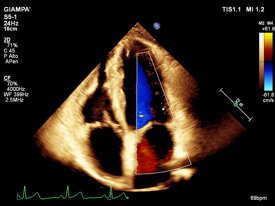

Dr. Arcangelo Giampa’ specialista cardiologo presso UMIMED Centro Medico Castagna di Darfo Boario Terme, ASST Valcamonica e ASST Spedali Civili di Brescia. Ho al mio attivo una vasta esperienza nel settore cardiologico in ambito clinico e nella diagnostica strumentale non invasiva ed ho partecipato a numerosi eventi in ambito nazionale ed internazionale.

con i nuovi software di intelligenza artificiale e imaging vascolare tridimensionale